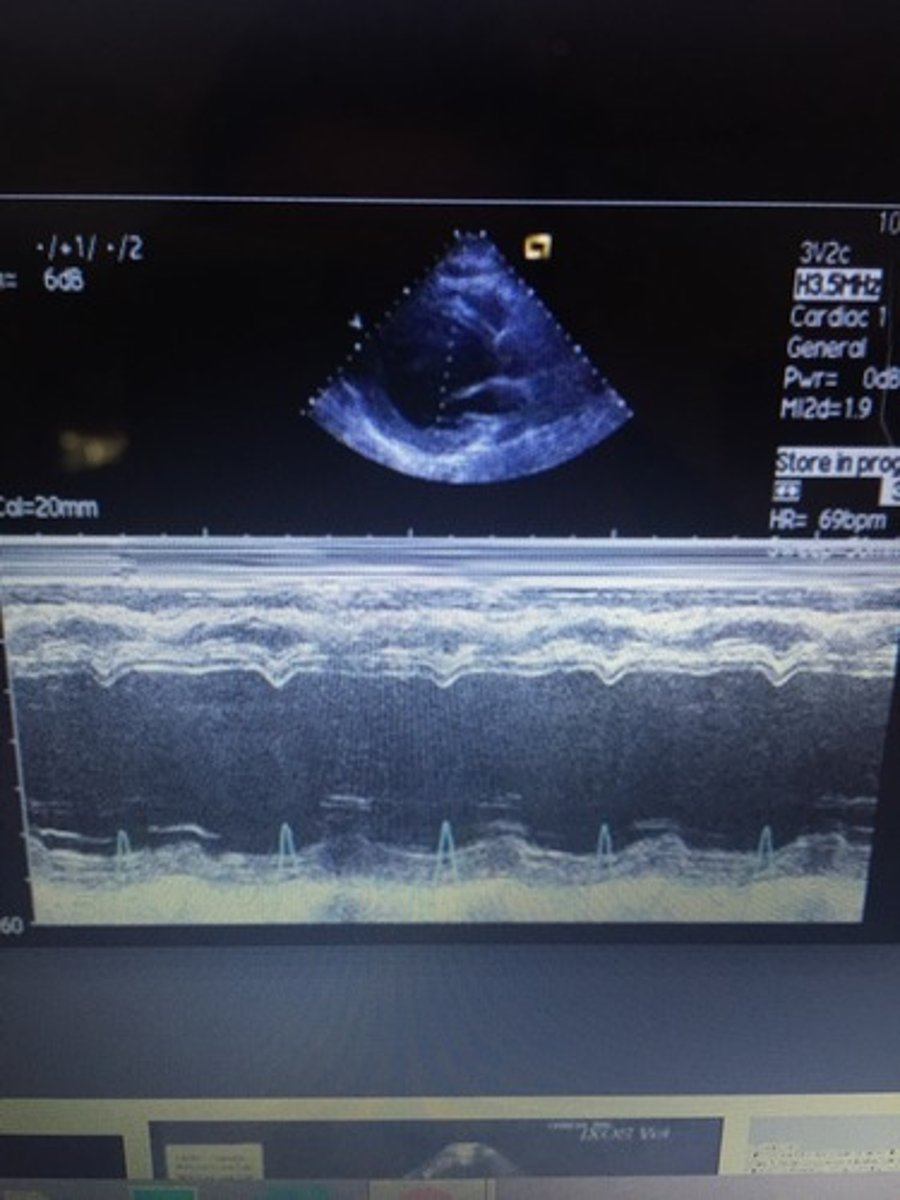

LV dilation with poorly contracting septal or posterior walls; EPSS >10mm/s and decreased EF%; leads to congestive heart failure

dilated cardiomyopathy